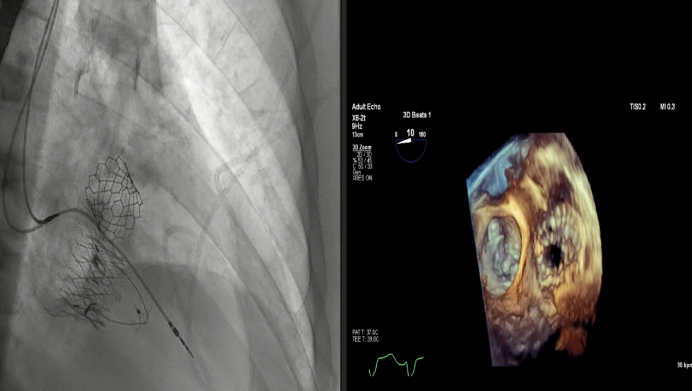

2023年美國心血管研究技術(shù)年度研討會(CRT)在美國華盛頓舉行。作為全球心臟瓣膜介入治療領(lǐng)域的頂級盛會之一,CRT吸引著來自全球瓣膜領(lǐng)域?qū)<覍W(xué)者的目光。在本次大會上,來自法國CHU de Bordeaux的Thomas Modine教授和來自美國Henry Ford Hospital的Dee Dee Wang教授分別報告了關(guān)于通過頸內(nèi)靜脈放置Lux-Valve Plus的早期數(shù)據(jù)和Lux-Valve Plus術(shù)中的超聲指引經(jīng)驗。

Dee Dee Wang教授分享了Henry Ford Hospital前4例Lux-Valve Plus的植入經(jīng)驗,并提示術(shù)中確定瓣葉夾持鍵的位置處于三尖瓣瓣環(huán)下方(右心室側(cè)),以及室間隔固定片與室間隔的相對位置關(guān)系是最關(guān)鍵的兩個步驟。使用經(jīng)胃底短軸切面,有時配合右室流入/流出道切面的X-plane就能較容易地獲取相關(guān)影像。由于Lux-Valve Plus對超聲影像的要求較低,手術(shù)過程會相對比較流暢。